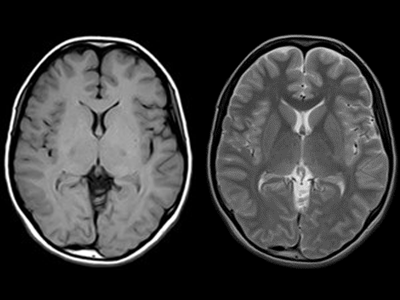

専用 脳MRI 3 高性能MRI(1.5テスラ)|施設・設備|おおたけ脳神経・漢方内科の詳細情報

高性能MRI(1.5テスラ)|施設・設備|おおたけ脳神経・漢方内科。今回導入された3T-MRIについて|名古屋セントラル病院。1.5T MAGNETOM ESSENZA 頭頸部領域における質の高い診断と検査。

「脳MRI3」

MRI | 三島総合病院 | 地域医療機能推進機構